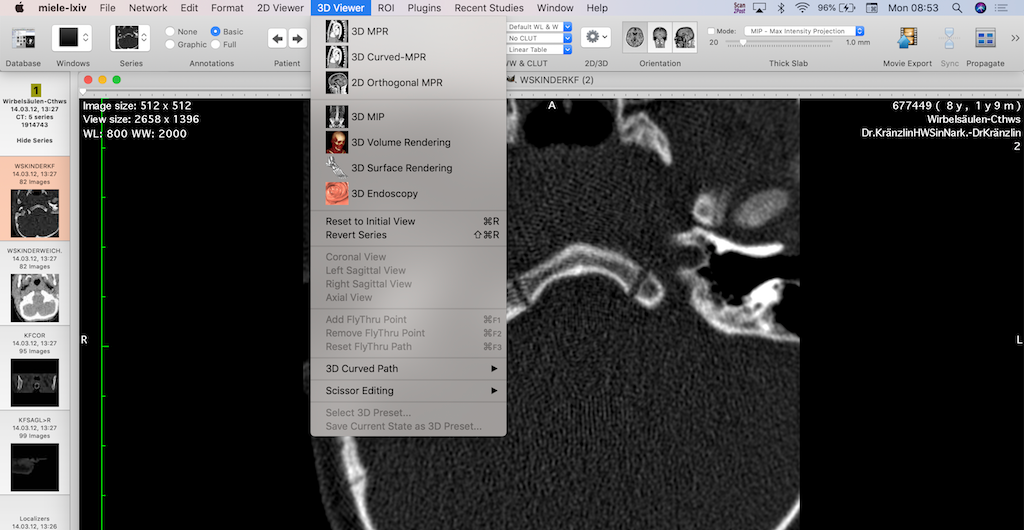

Another area where AI is transforming radiology is in the speed and efficiency of image processing. Traditional methods of image analysis can be time-consuming, often requiring hours or days for detailed examination and interpretation. AI, however, can process vast amounts of data in a fraction of the time, providing quicker results without sacrificing accuracy.

This speed is especially valuable in emergency situations where time is critical. For instance, in the case of stroke patients, immediate and accurate identification of brain abnormalities is essential to begin life-saving treatments. AI algorithms can quickly analyze brain scans, identifying issues such as blood clots or hemorrhages in real time, allowing medical teams to respond faster and with greater confidence.

In addition, AI-driven automation in medical imaging helps reduce the workload for radiologists, who often face high volumes of cases daily. By automating routine tasks such as image sorting, measurements, and preliminary analysis, AI frees up radiologists to focus on more complex cases that require human expertise. This leads to increased efficiency in radiology departments and enables faster diagnosis for patients.